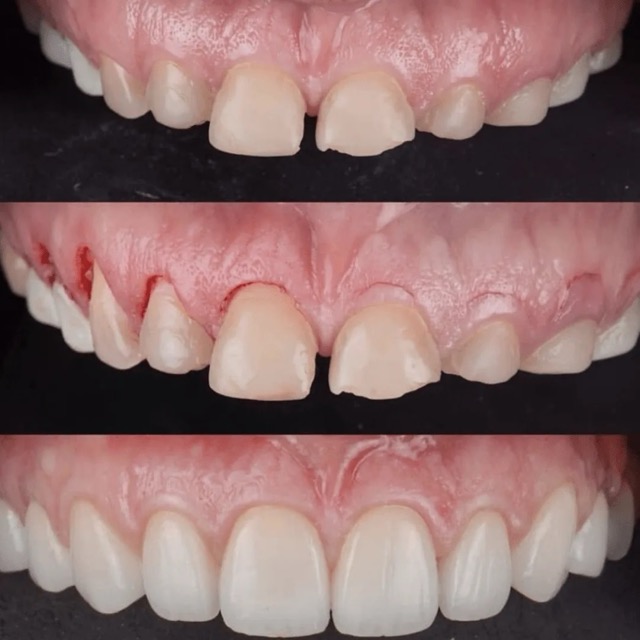

Patient presented to the office with trauma to front two teeth several weeks ago causing her severe pain. After a thorough clinical exam which included endodontic screening and proper x rays led to the diagnosis of necrotic (dead) pulp tissue due to the force of trauma.

Root canals were performed and highly aesthetic Emax crowns were fabricated to meet the patient’s desire to maintain the natural smile and contour as was before the trauma.